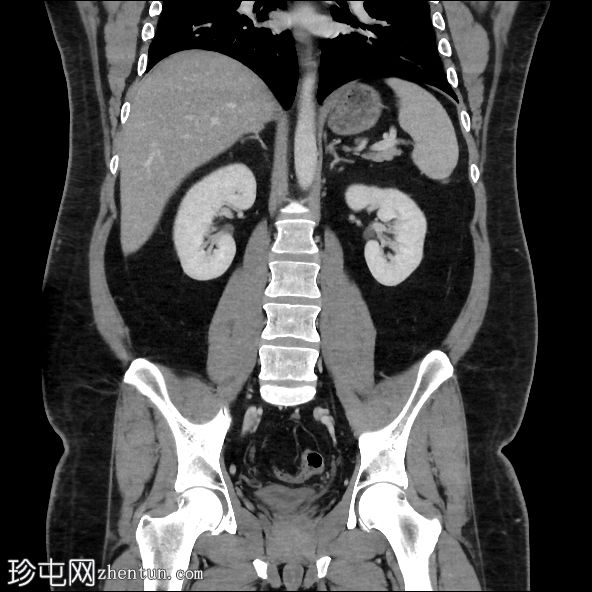

轴向C+门静脉期

冠状C+门静脉期

肝脏脂肪变性,伴地图样脂肪沉积。胆囊扩张,胆囊壁增厚,周围浑浊,胆囊颈结石,胆囊前壁凹陷(胆底张力征)。

本病例展示了CT扫描在急性胆囊炎(通常是意外诊断)诊断中的价值。CT扫描通常比

检查更具评估价值,因为能够更准确地识别脂肪条带。胆囊底张力征提示胆囊受阻并承受压力,因为它会凹陷(而不是顺应)前腹壁。